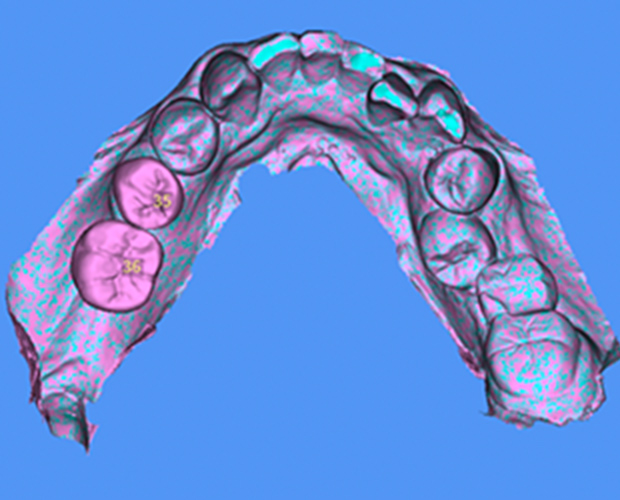

SMOP

スモップ

インプラント治療におけるコンピューターガイドシステムの一つで、CT診断によるシミュレーションを実際の口腔内で再現いたします。

これにより、より正確なインプラント埋入が可能になり、患者の負担を軽減する手術(フラップレス手術)も行える場合があります

特徴

• マッチング精度の徹底的追求

• 口腔内での適合度の追求

• さまざまな症例に対応

• 部分的骨支持にも対応可能

• インプラントシステムの多くに対応

• 複数のウィンドウ作製可能